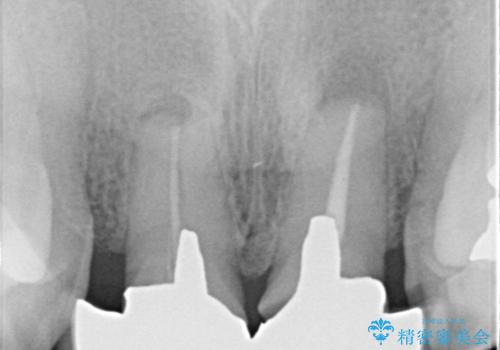

- 前歯の被せもののやりかえを主訴に来院されました。

前歯の歯茎から膿も出ていたため、歯内治療を行なったのち修復を行なっております。

根管治療および外科的歯内療法を行なってから被せものの処置を行なっております。